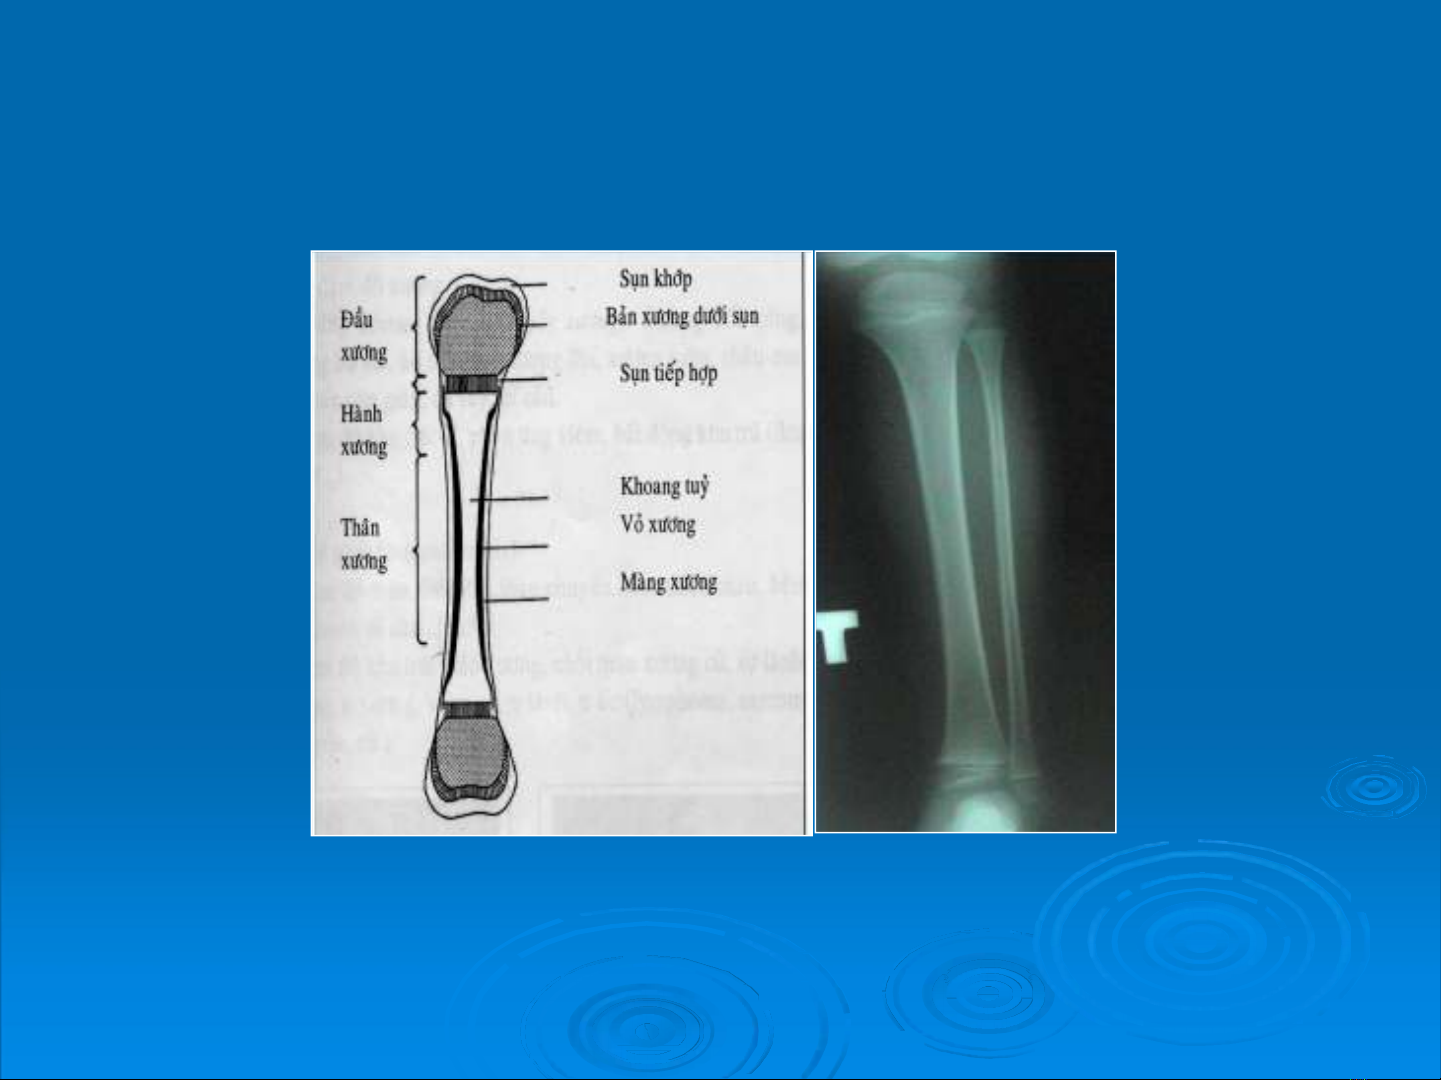

II. U xương lành tính

1.U tổ chức tạo xương

a.U xương lành tính (osteoma)

- N/n: Có thể do chấn thương, do di truyền hoặc do

rối loạn phát triển xương.

- Vị trí hay gặp: Xương sọ, xoang mặt và các chi.

- Hình ảnh :

+ U thường đơn độc.

+ Hình mờ đậm đồng đều, các xương mọc thêm

cũng thấy rõ thớ xương.

+ Hình tròn hoặc bầu dục, bờ viền liên tục rõ nét.

+ Không bao giờ có hình ảnh viêm màng xương.